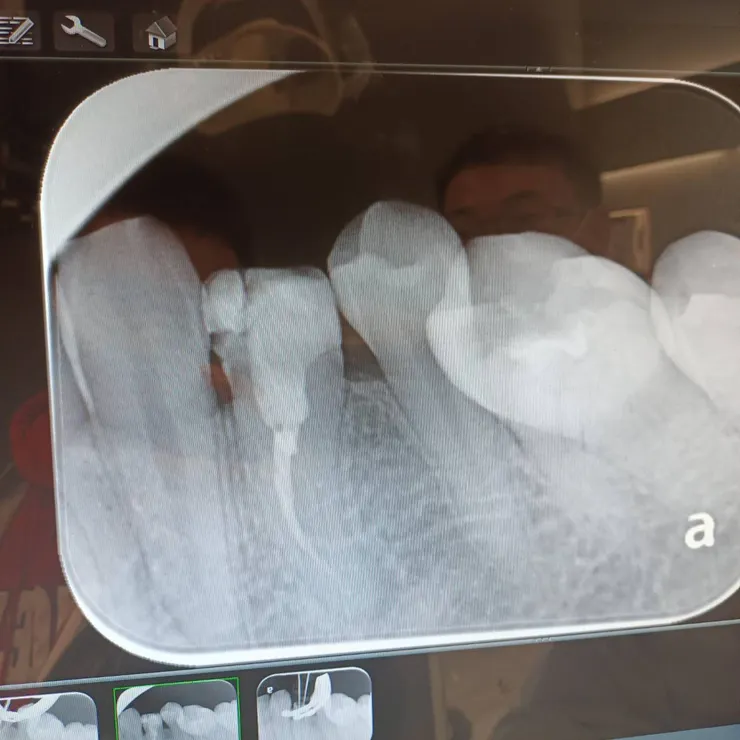

兩根根管的樣子

根管被填起來的樣子